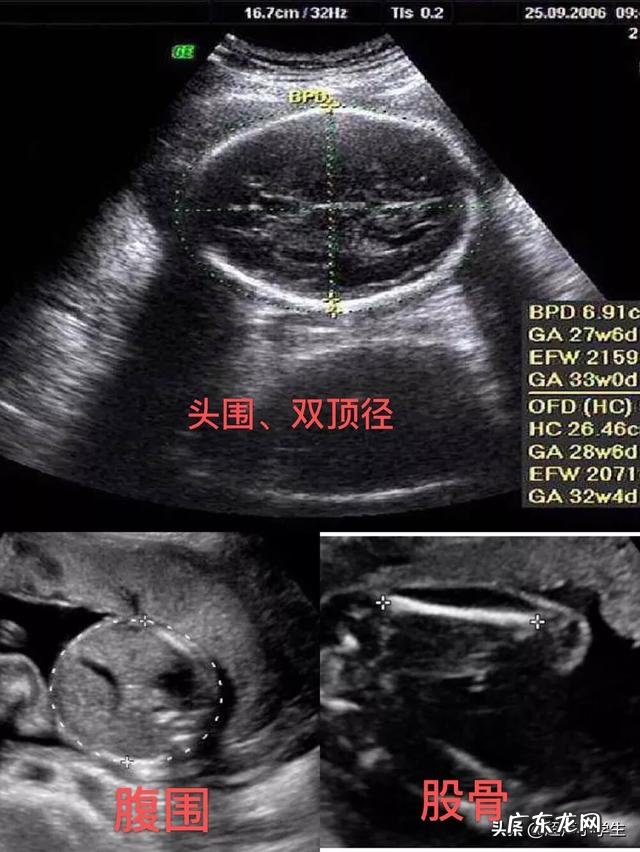

另外 , B超单子上的预产期都是通过测量胎儿各方面发育综合评估而来的 , 因此可能并不是很准确 。

我怀过两次孕 , 其中一次就忘记了末次月经的时间 , 本来以为检查一下B超就可以知道孕周了 , 医生却说其实越到孕晚期B超估算预产期越不准确 。

记得我生我家二宝的时候 , 如果按照末次月经时间算我其实已经怀孕40周多了 , 可那天我做B超 , B超上的孕周却显示的是38周 , 然后我问医生 , 医生就说B超估算的预产期并不是很准确 。

怀孕之后 , 预产期成为妈妈们关心的问题之一 , 第一次做产检的时候 , 医生会根据你的末次月经时间计算得出预产期 , 而B超报告上也会出现一个怀孕时间 , 可能这个怀孕时间与你计算的怀孕时间有差别 , 有些妈妈就开始疑惑:预产期是按着医生计算的那个时间还是按着B超单上表示的怀孕时间推算?

有些孕妈看到B超单上的怀孕时间与计算的预产期时间有出入会觉得奇怪 , 其实这很正常: